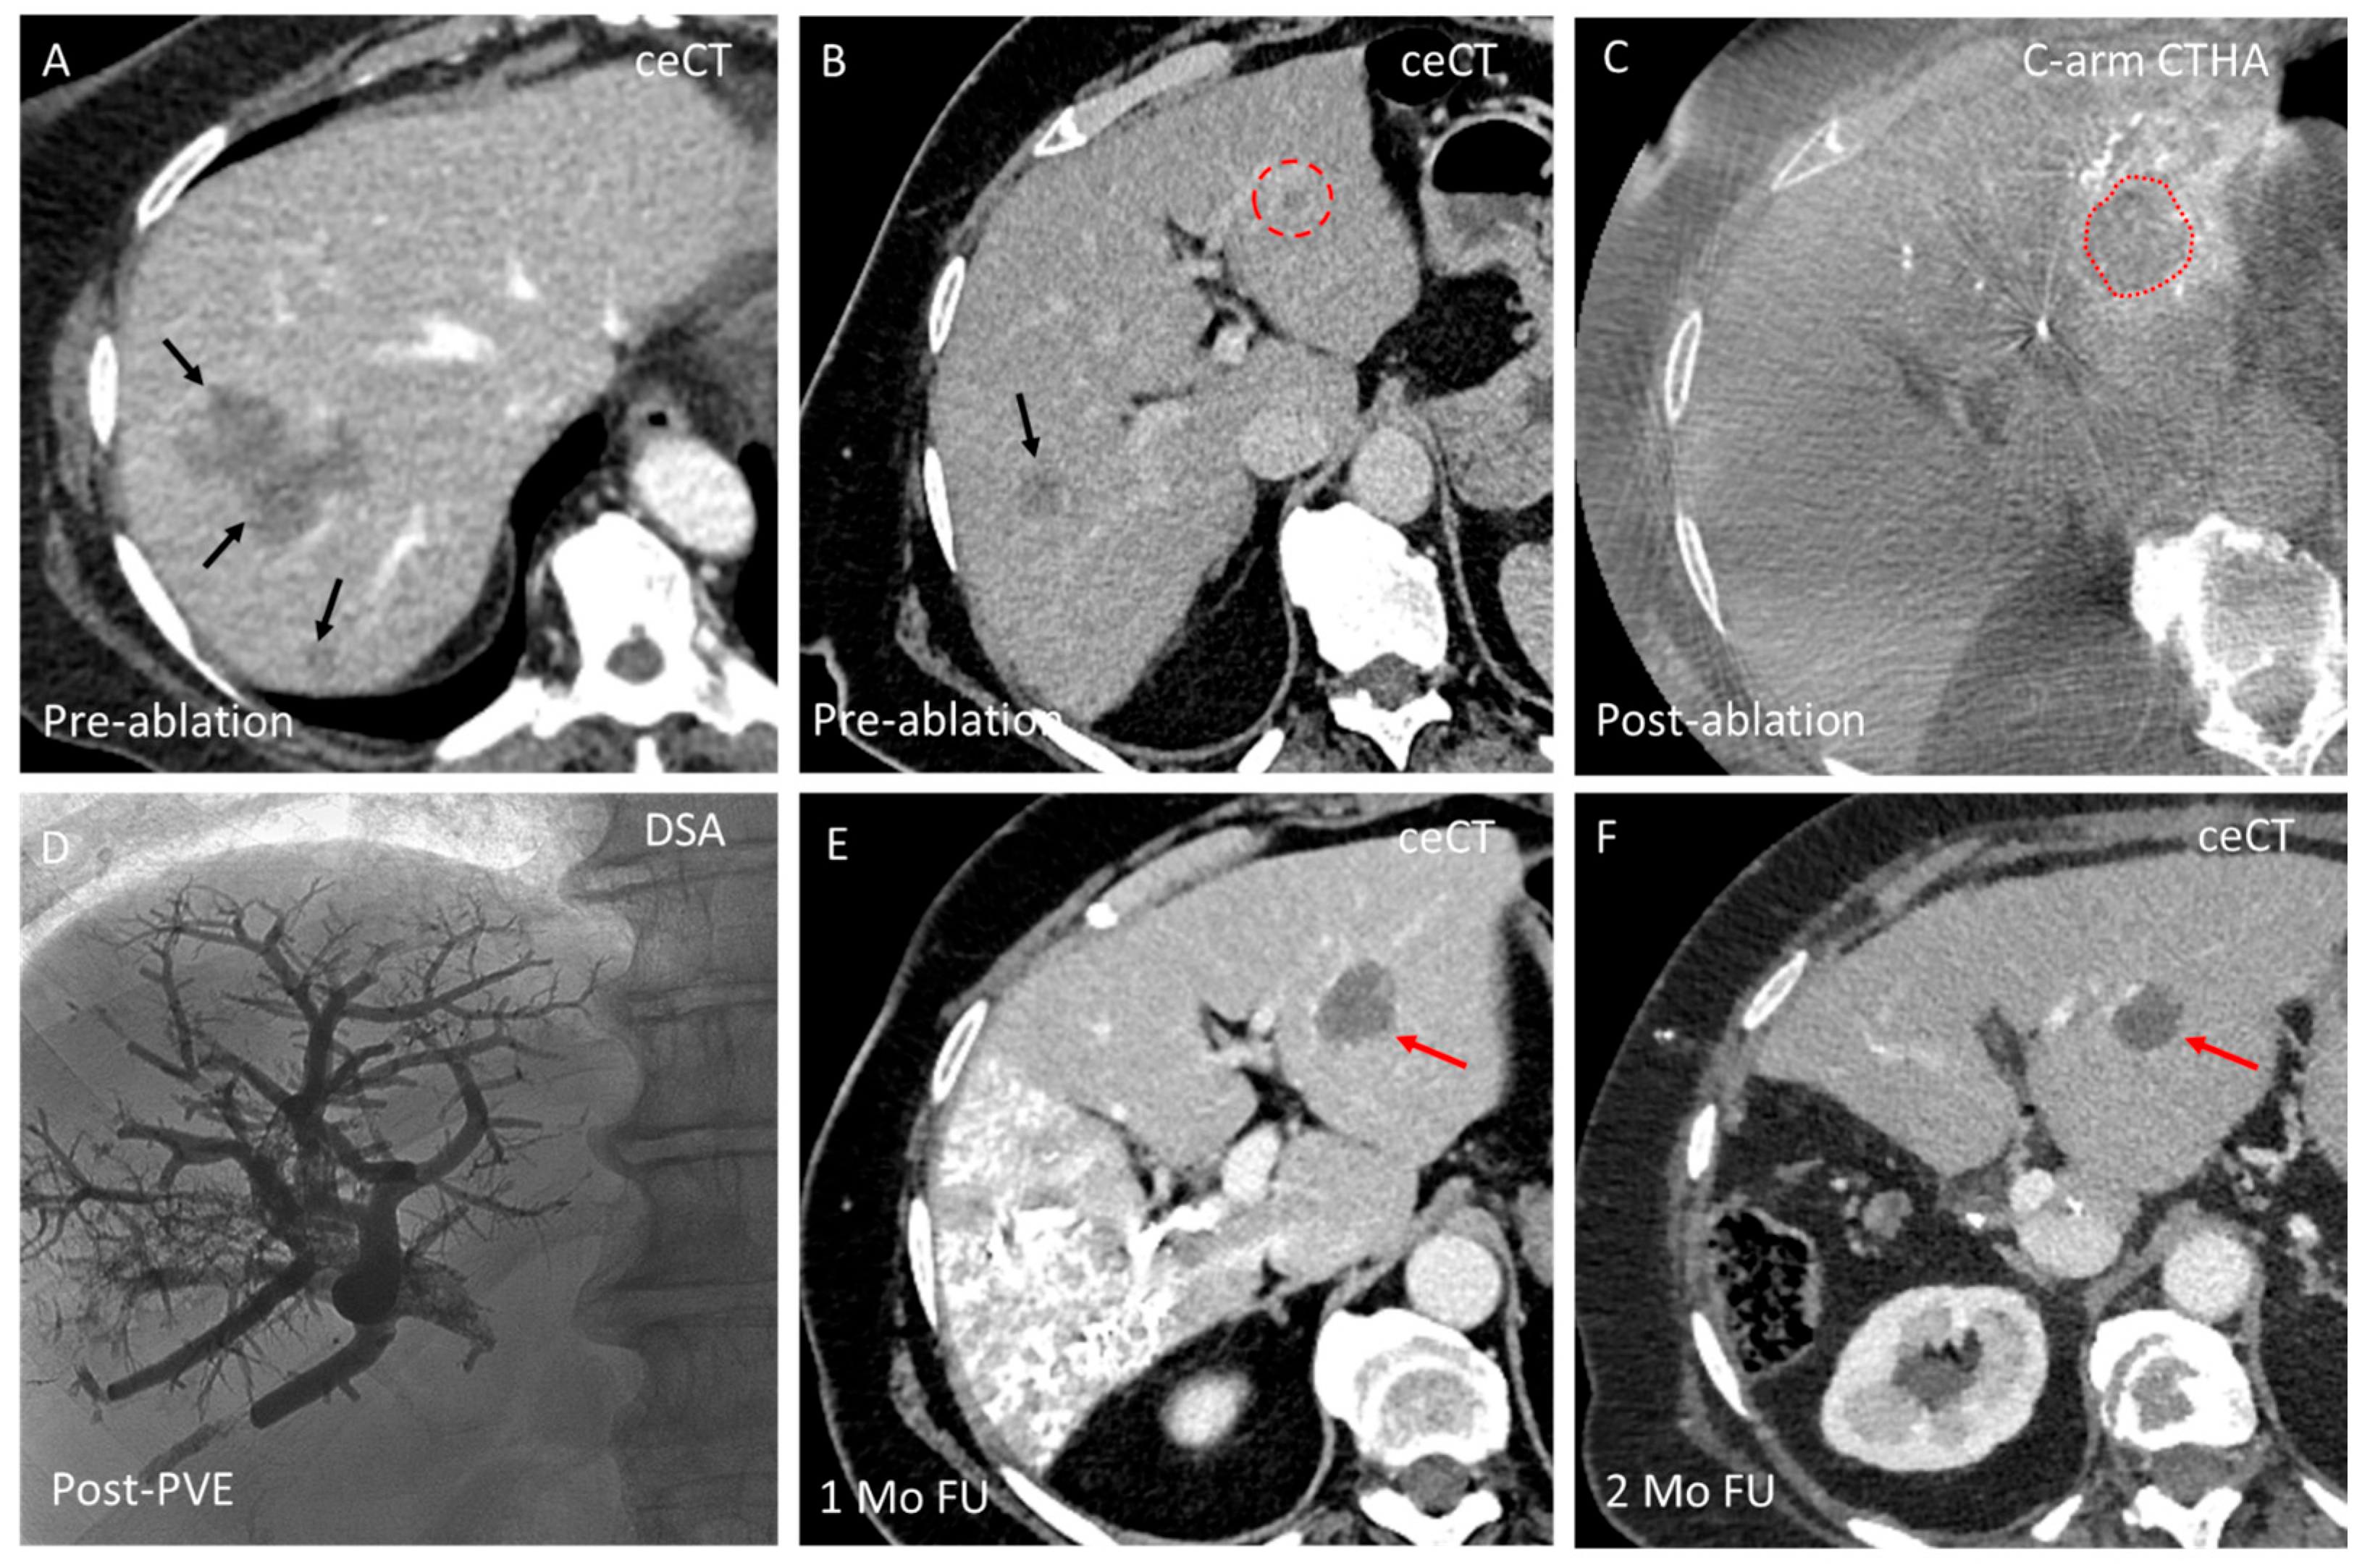

3.2. Domain B—Single-Session Combination of Ablation with Endovascular Treatment